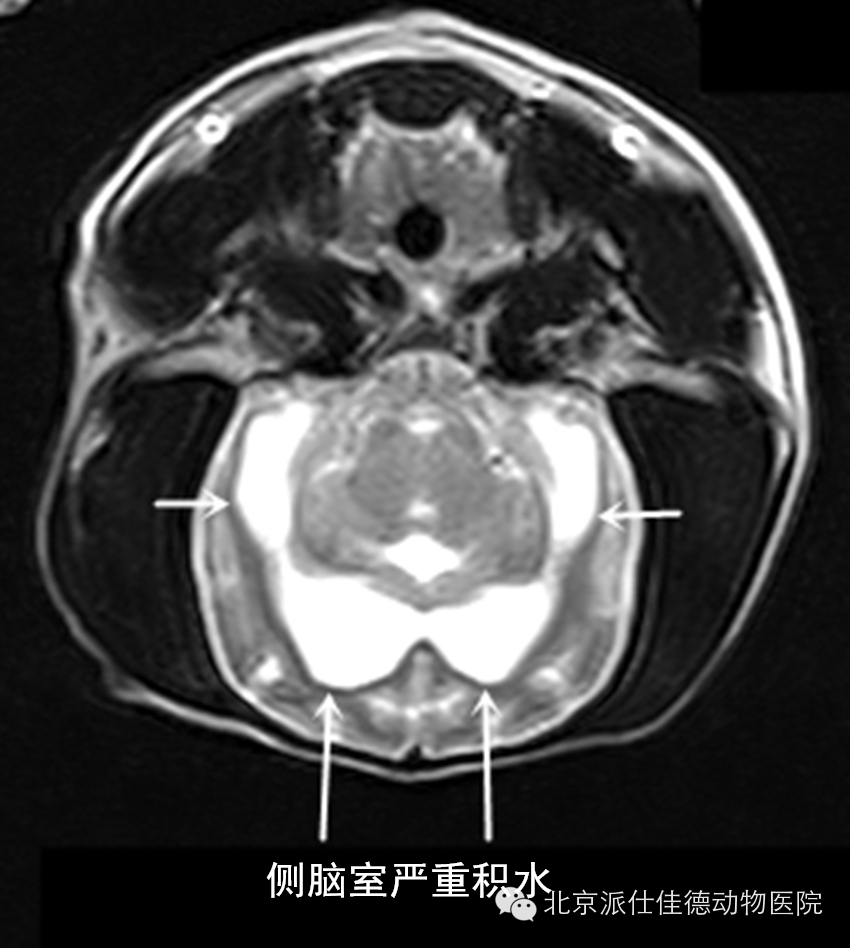

16.有些动物表现为突发癫痫,不停的抽搐,经核磁共振扫描发现脑积水、脑炎、脑肿瘤等等。